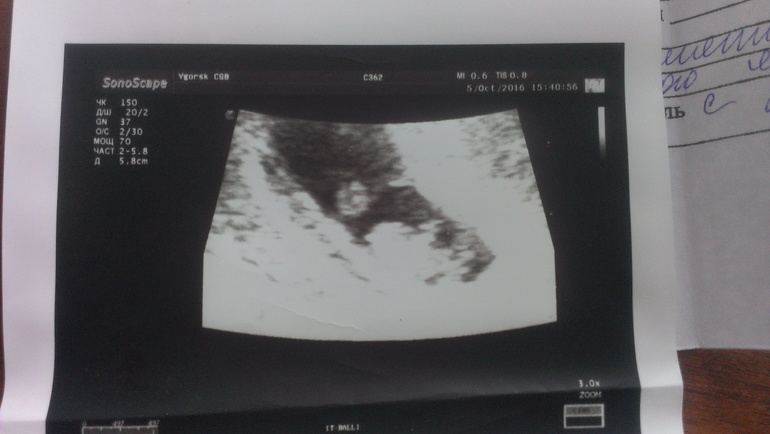

Начну с самого плохого. Мы с мужем разошлись, сейчас в процессе развода. Долгое время уже не живем вместе, за это время я встретила мужчину - Андрея. На самом деле мы давно знакомы, он мой бывший одноклассник, в школе пытался за мной ухаживать, а вот теперь свела судьба) сам недавно развелся. В общем мы начали встречаться) Макушку он полюбил буквально, как свою) Но тут я узнаю, что беременна! Конечно, первой мыслью было прервать беременность: я не знала, как Андрей отреагирует, да и вообще боялась ему говорить, понятия не имела, как я буду справляться одна с погодками.. Но я все-таки взяла себя в руки и поговорила с Андреем. На мое удивление, он воспринял новость очень хорошо и сразу предложил жить вместе, познакомил со своими родителями) я подала на развод с мужем. Конечно, все вокруг в шоке, что я решилась рожать (мама до сих пор уговаривает на аборт), ведь Андрея толком не знаю, не знаю, к чему приведут наши отношения, но почему-то я верю, что все будет хорошо))) Итак сейчас я на 11 неделе по М, 5 октября была УЗИ, поставили срок 7,6 нед. Моей уже старшей дочери 9,5 месяцев. Я буду мамой погодок))) пока самой не верится)))

А вот и моя маленькая неожиданность: